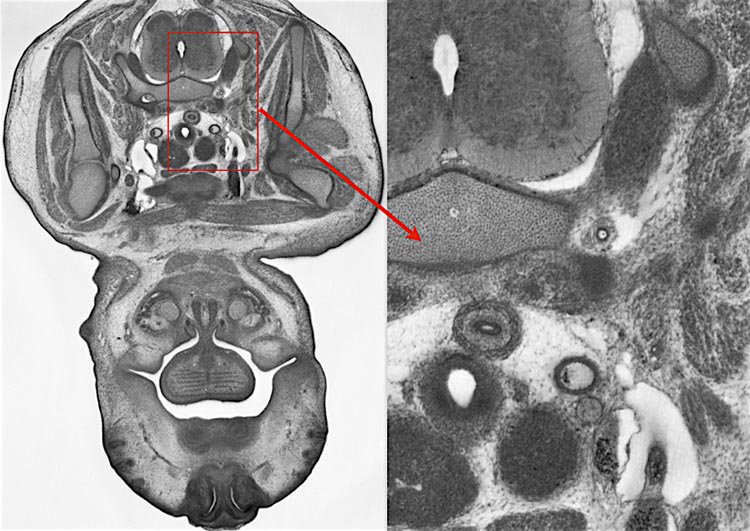

The DMDD research programme produced a free, online database of embryonic-lethal mouse gene knockouts, including high-resolution 3D images and phenotype data.

Former Deciphering Mechanisms of Developmental Disorders project members in Vienna are running a 2 day workshop on HREM imaging, its applications, sample preparation, data generation and analysis, challenges and limitations. 23-24 May 2019. blog.dmdd.org.uk/hrem-workshop/ #hrem #imaging #development #Microscopy

The other is out Nature Communications doi.org/10.1038/s41467… This work was part of the Deciphering Mechanisms of Developmental Disorders programme which has phenotyped embryonic lethal mouse mutants. (1/11)